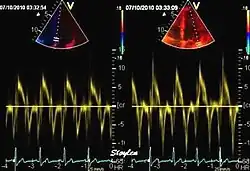

Colour tissue Doppler

Colour tissue Doppler traces from a normal subject Left: traces from the septum and mitral ring. The similarities of the curve shape to spectral Doppler is evident. Right: multiple traces from sites along the septum. The decreasing velocities from base to apex is evident.

Unlike spectral Doppler, colour tissue Doppler samples velocities from all points of the sector, by shooting two pulses successively, and calculating the velocity from the phase shift between them by autocorrelation. The calculation is slightly different from the true Doppler effect, but the result becomes identical. This results in a single velocity value per sample volume. The result is a velocity field of (nearly) simultaneous velocity vectors towards the probe. The advantage of colour Doppler over spectral Doppler is that all velocities can be sampled simultaneously. The disadvantage is that if there is clutter noise (stationary reverberations), the stationary echoes will be integrated in the velocity calculation, resulting in an under estimate. As pulsed wave Doppler are displayed as a spectrum, the colour Doppler values will correspond to the mean of the spectrum (in the absence of clutter), giving slightly lower values. In the HUNT study, the difference in peak systolic values were about 1.5 cm/s.[26]

The local velocities are not the result of the local function, as segments are moved by the action of neighbouring segments. Thus the velocity differences velocity gradient are the main measure of regional contraction, and has become the most important employment of colour tissue Doppler, in the method of strain rate imaging.[27]